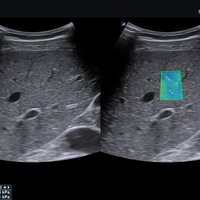

Das X-CUBE 70 bietet modernste Technologien für eine objektive und akkurate Diagnose. Intelligente klinische Module heben das System auf ein neues diagnostisches Niveau. Es erweitert Ihre Fähigkeiten und die Bandbreite Ihrer Möglichkeiten. Dazu gehören Module wie MicroView, point Shear Wave Elastographie (pSWE), oder auch die Kontrastmittelsonographie.